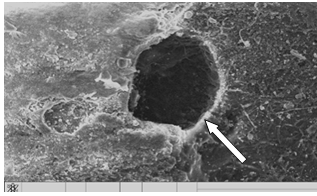

. Исследование морфологии огнестрельных переломов пластинчатых и

трубчатых костей методом сканирующей электронной микроскопии (50 образцов).

трубчатых костей методом атомно-силовой микроскопии (25 образцов).